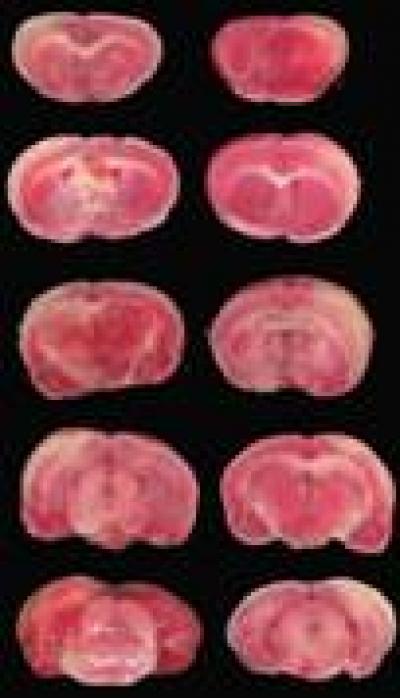

The individual difference and non-repeatability in acupuncture have not only restricted the development of acupuncture, but have also affected the specificity of acupoints. As reported in a recent study published in the Neural Regeneration Research (Vol. 8, No. 28, 2013), acupuncture at Neiguan (PC6) was performed using a custom lifting- and thrusting-controlled machine. A frequency of 1, 2, or 3 Hz and duration of 5, 60, or 180 seconds were used to observe cerebral blood flow and ratio of infarct volume recovery. An orthogonal design was used to sift the optimal parameter of Neiguan acupuncture. Experimental results showed that stimulation at Neiguan with a frequency of 1 Hz and long duration of 180 seconds or 2/3 Hz and long duration of 5/60 seconds significantly increased cerebral blood flow and decreased the ratio of infarct volume.